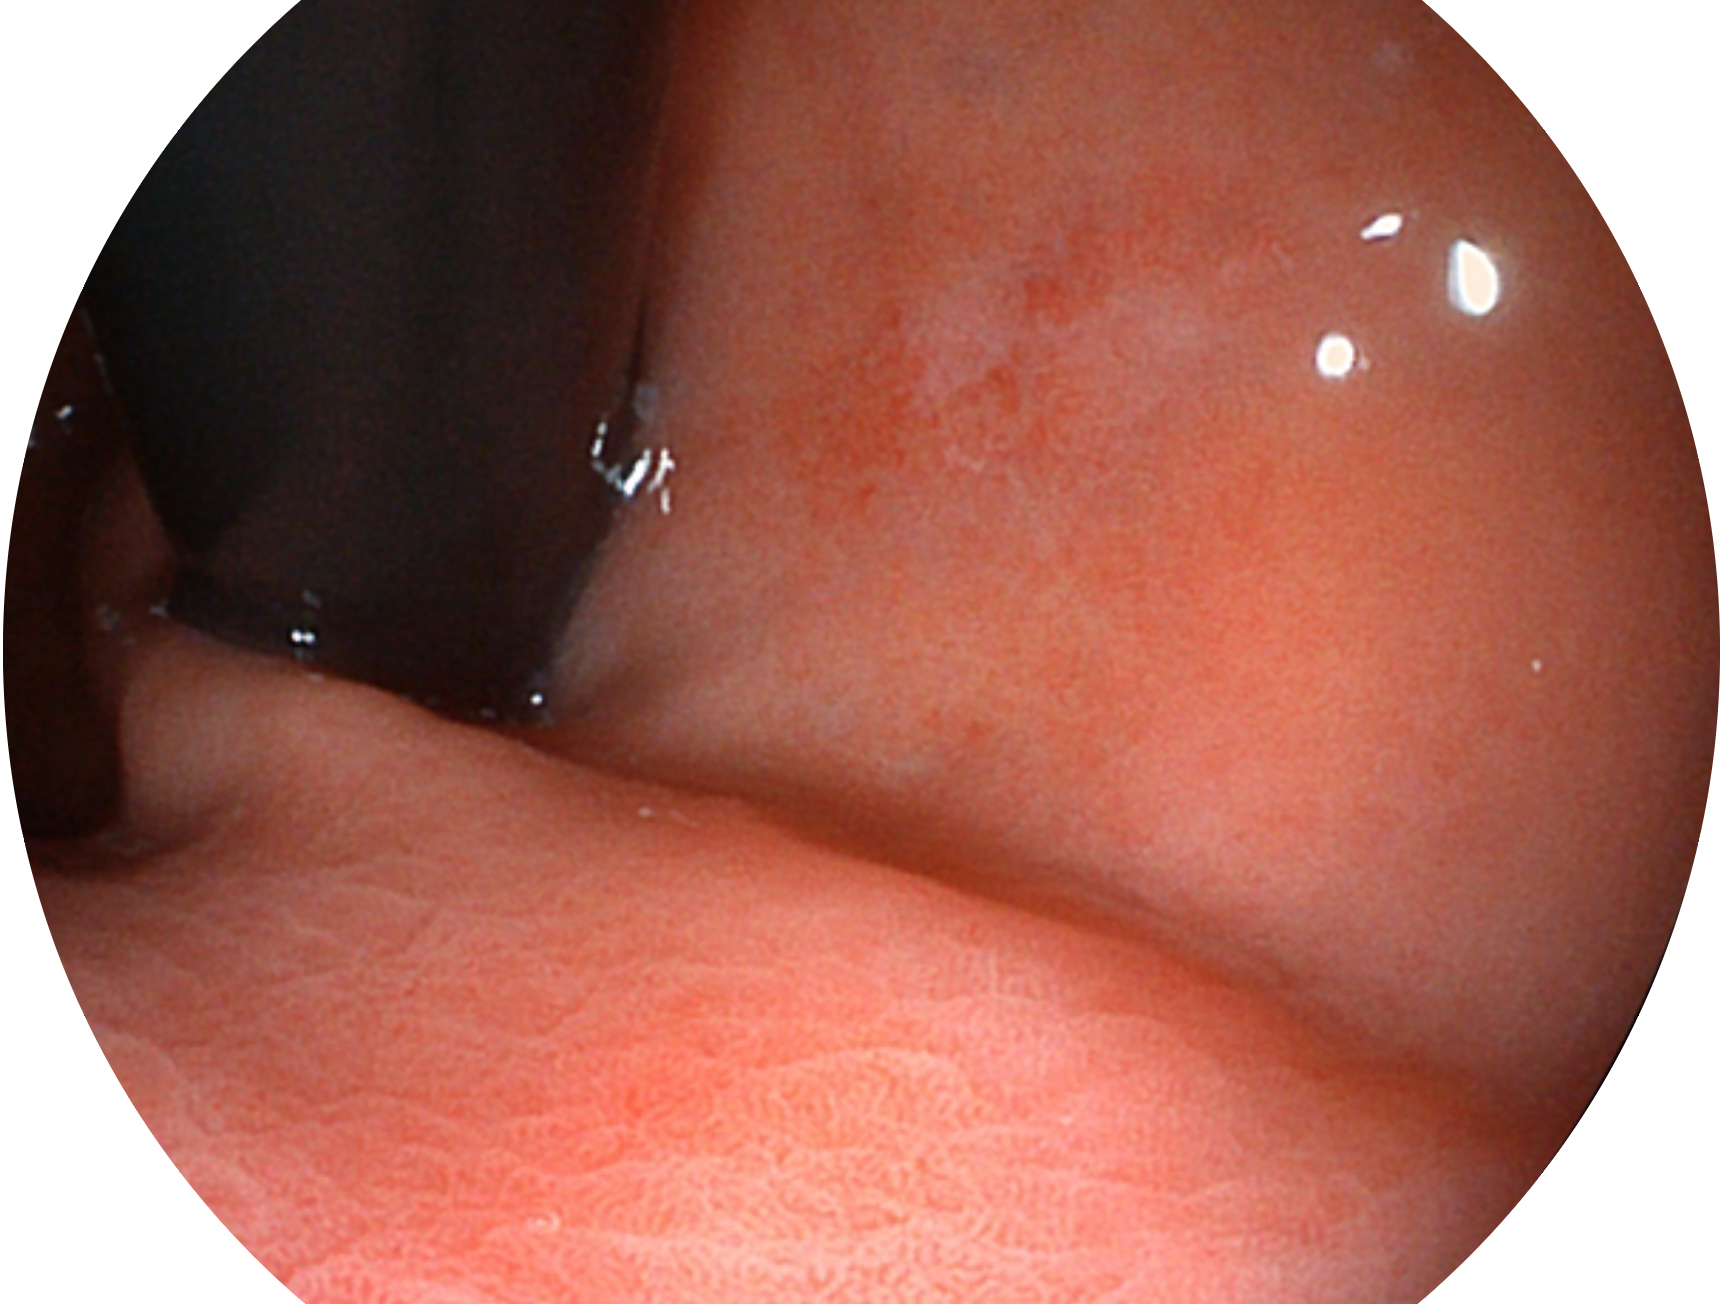

乐玩lewin国际新开发的内镜染色技术,主要是基于多波长LED 光源的开发,VLS-55Q 四波长LED 光源是由四个不同颜色的LED光按照相应照明模式所规定的特定发光比例进行合束后形成,合束后形成的照明光的光谱由红光、绿光、蓝光及蓝紫光这四个不同的波段范围构成。具有更高光谱自由度,通过光谱比例的控制,实现了聚谱成像技术,英文全称为“Spectral Focused Imaging, SFI”,缩写为“SFI”和光电复合染色成像技术,英文全称为“Versatile Intelligent Staining Technology, VIST”,缩写为“VIST”。